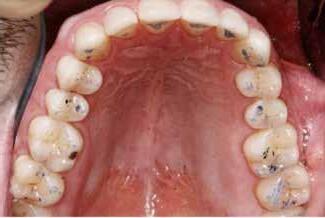

Okklusalt billede af A) over- og B) underkæbe

2. Klinisk ses tydelig slitage ind i dentinen på samtlige tænder fra 6’er til 6’er i begge kæber.

Fig. 2. Clinically, extensive wear into the dentin of all teeth in both jaws is observed.